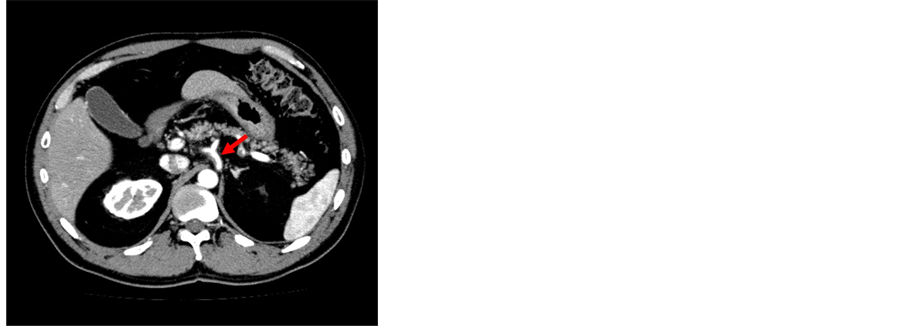

Figure 2. Case 2. (A) Abdominal CT with contrast injection showing an aneurysm of the celiac artery 18 mm in diameter. The presence of dissection is unclear; (B) Transverse section of the celiac artery at low magnification (Weigert staining revealing elastic fibers). The cleavage plane is located in the elastic layer which is thick with chronic change. T, True lumen; F, False lumen; (×10).

A celiac artery aneurysm was observed incidentally in a 65-year-old woman by abdominal echography during health screening. She had no risk factors for cardiovascular disease. Enhanced CT and aortography revealed a celiac artery aneurysm, which was 18mm in diameter (Figure 2(A)). And no dissection of the aorta around celiac axis was observed. Surgery was performed under patient’s informed choice. After laparotomy, we dissected the lesser omentum and approached the celiac artery aneurysm. The outward appearance of the aneurysm did not suggest dissection with chronic change. A test clamp of the celiac, common hepatic and splenic arteries caused only minor changes in the pulsation of the latter two. Therefore, we performed simple aneurysmectomy. The collateral circulation through the gastroduodenal and dorsal pancreatic arteries was preserved. Pathologic examination revealed that the common hepatic artery branched from the true lumen, and the splenic artery from the false lumen, respectively. Dissection of the celiac artery was demonstrated by histology with the cleavage plane located in the elastic layer which was thick with chronic change (Figure 2(B)). Little atherosclerotic or degenerative change was observed. The patient’s postoperative recovery was uneventful with resumption of normal alimentation. She was discharged 18 days after the operation, and postoperative course is well.